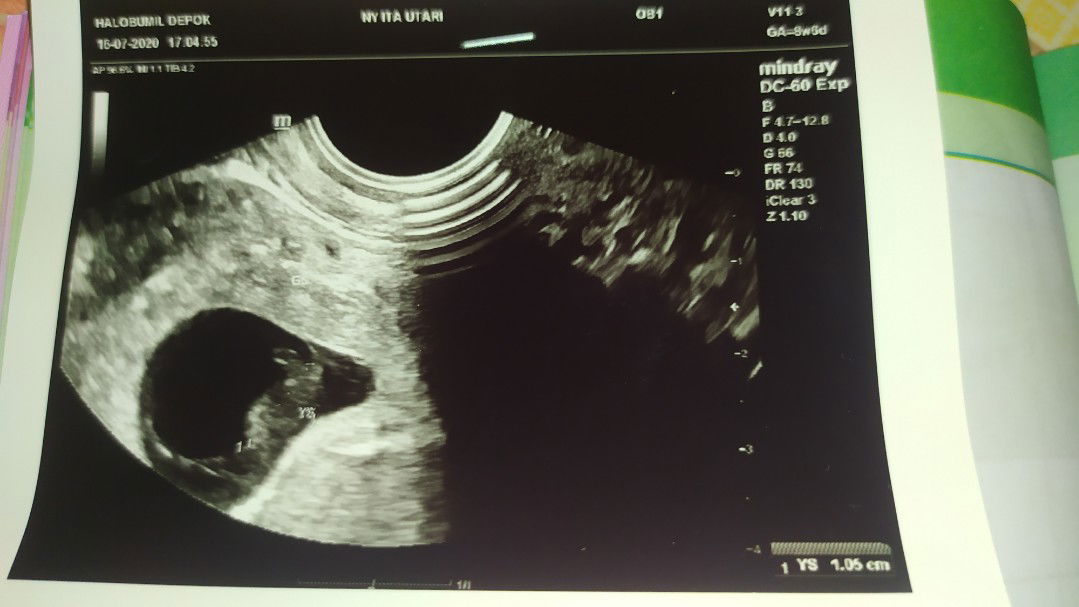

kehamilan pertamaku.β€οΈ

Alhamdulillah, setelah menikah kurang lebih 2 bulan langsung diberi kepercayaan untuk mengandung.π